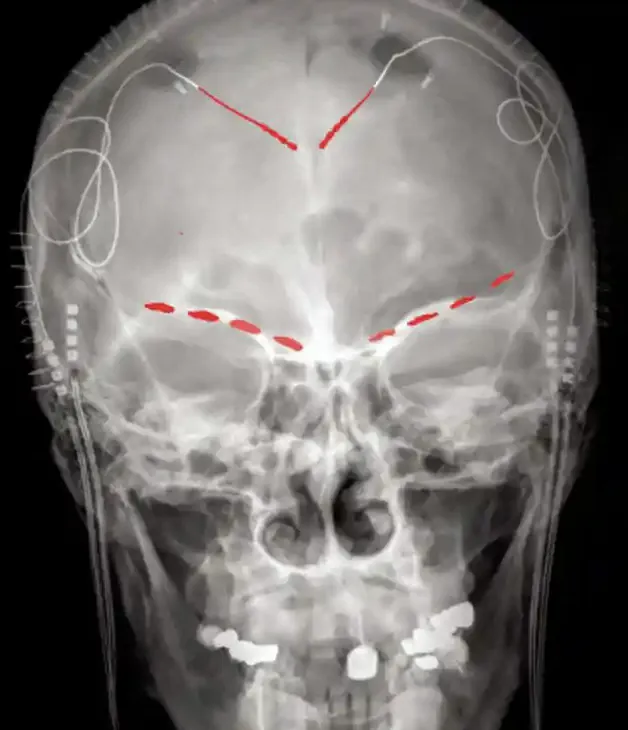

Các nhà khoa học đã phẫu thuật cấy ghép các điện cực vào 4 bệnh nhân bị đau mãn tính khó chữa. Các thiết bị này đã ghi lại hoạt động ở hai vùng não: vỏ não đai (ACC) và vỏ não quỹ đạo (OFC) chỉ bằng cách nhấn một nút trên thiết bị cầm tay từ xa (ảnh).

Qua cuộc khảo sát ngắn về cường độ và loại cơn đau mà 4 bệnh nhân đang trải qua, thiết bị ghi lại ảnh chụp nhanh về hoạt động não bộ của họ, cho thấy hoạt động não rất khác nhau đi kèm với cơn đau khác nhau. Việc giải mã được hoạt động của não gây ra cơn đau mãn tính làm dấy lên hy vọng sẽ có các liệu pháp kích thích não sâu có thể kiểm soát cơn đau mãn tính.